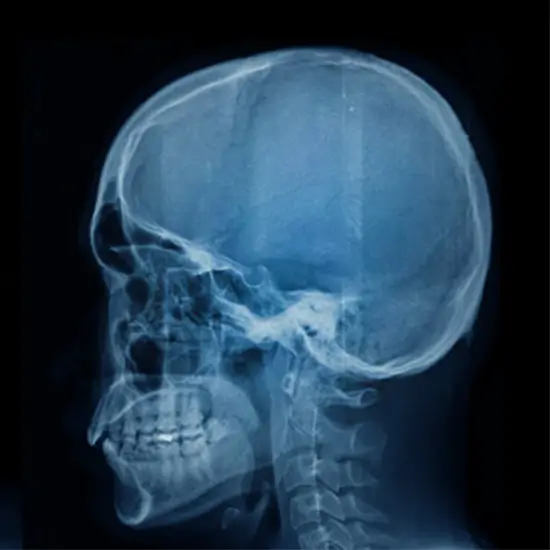

The Towne View test requires an X-ray in order to observe an angled AP radiograph of the skull and foramen sinus.

• To determine the degree of any damage caused by skull fractures.

• • To diagnose Paget's illness (destruction of bone followed by an extreme level of bone repair).

• • To assess acute mastoiditis (severe bacterial infection of the mastoid process).

• • To identify chronic sinusitis (sinus area enlargement) and otosclerosis (a genetic disorder causing deafness due to the extra bone formation in the inner ear).

• • To determine the severity of the stroke and bleeding in the brain area.